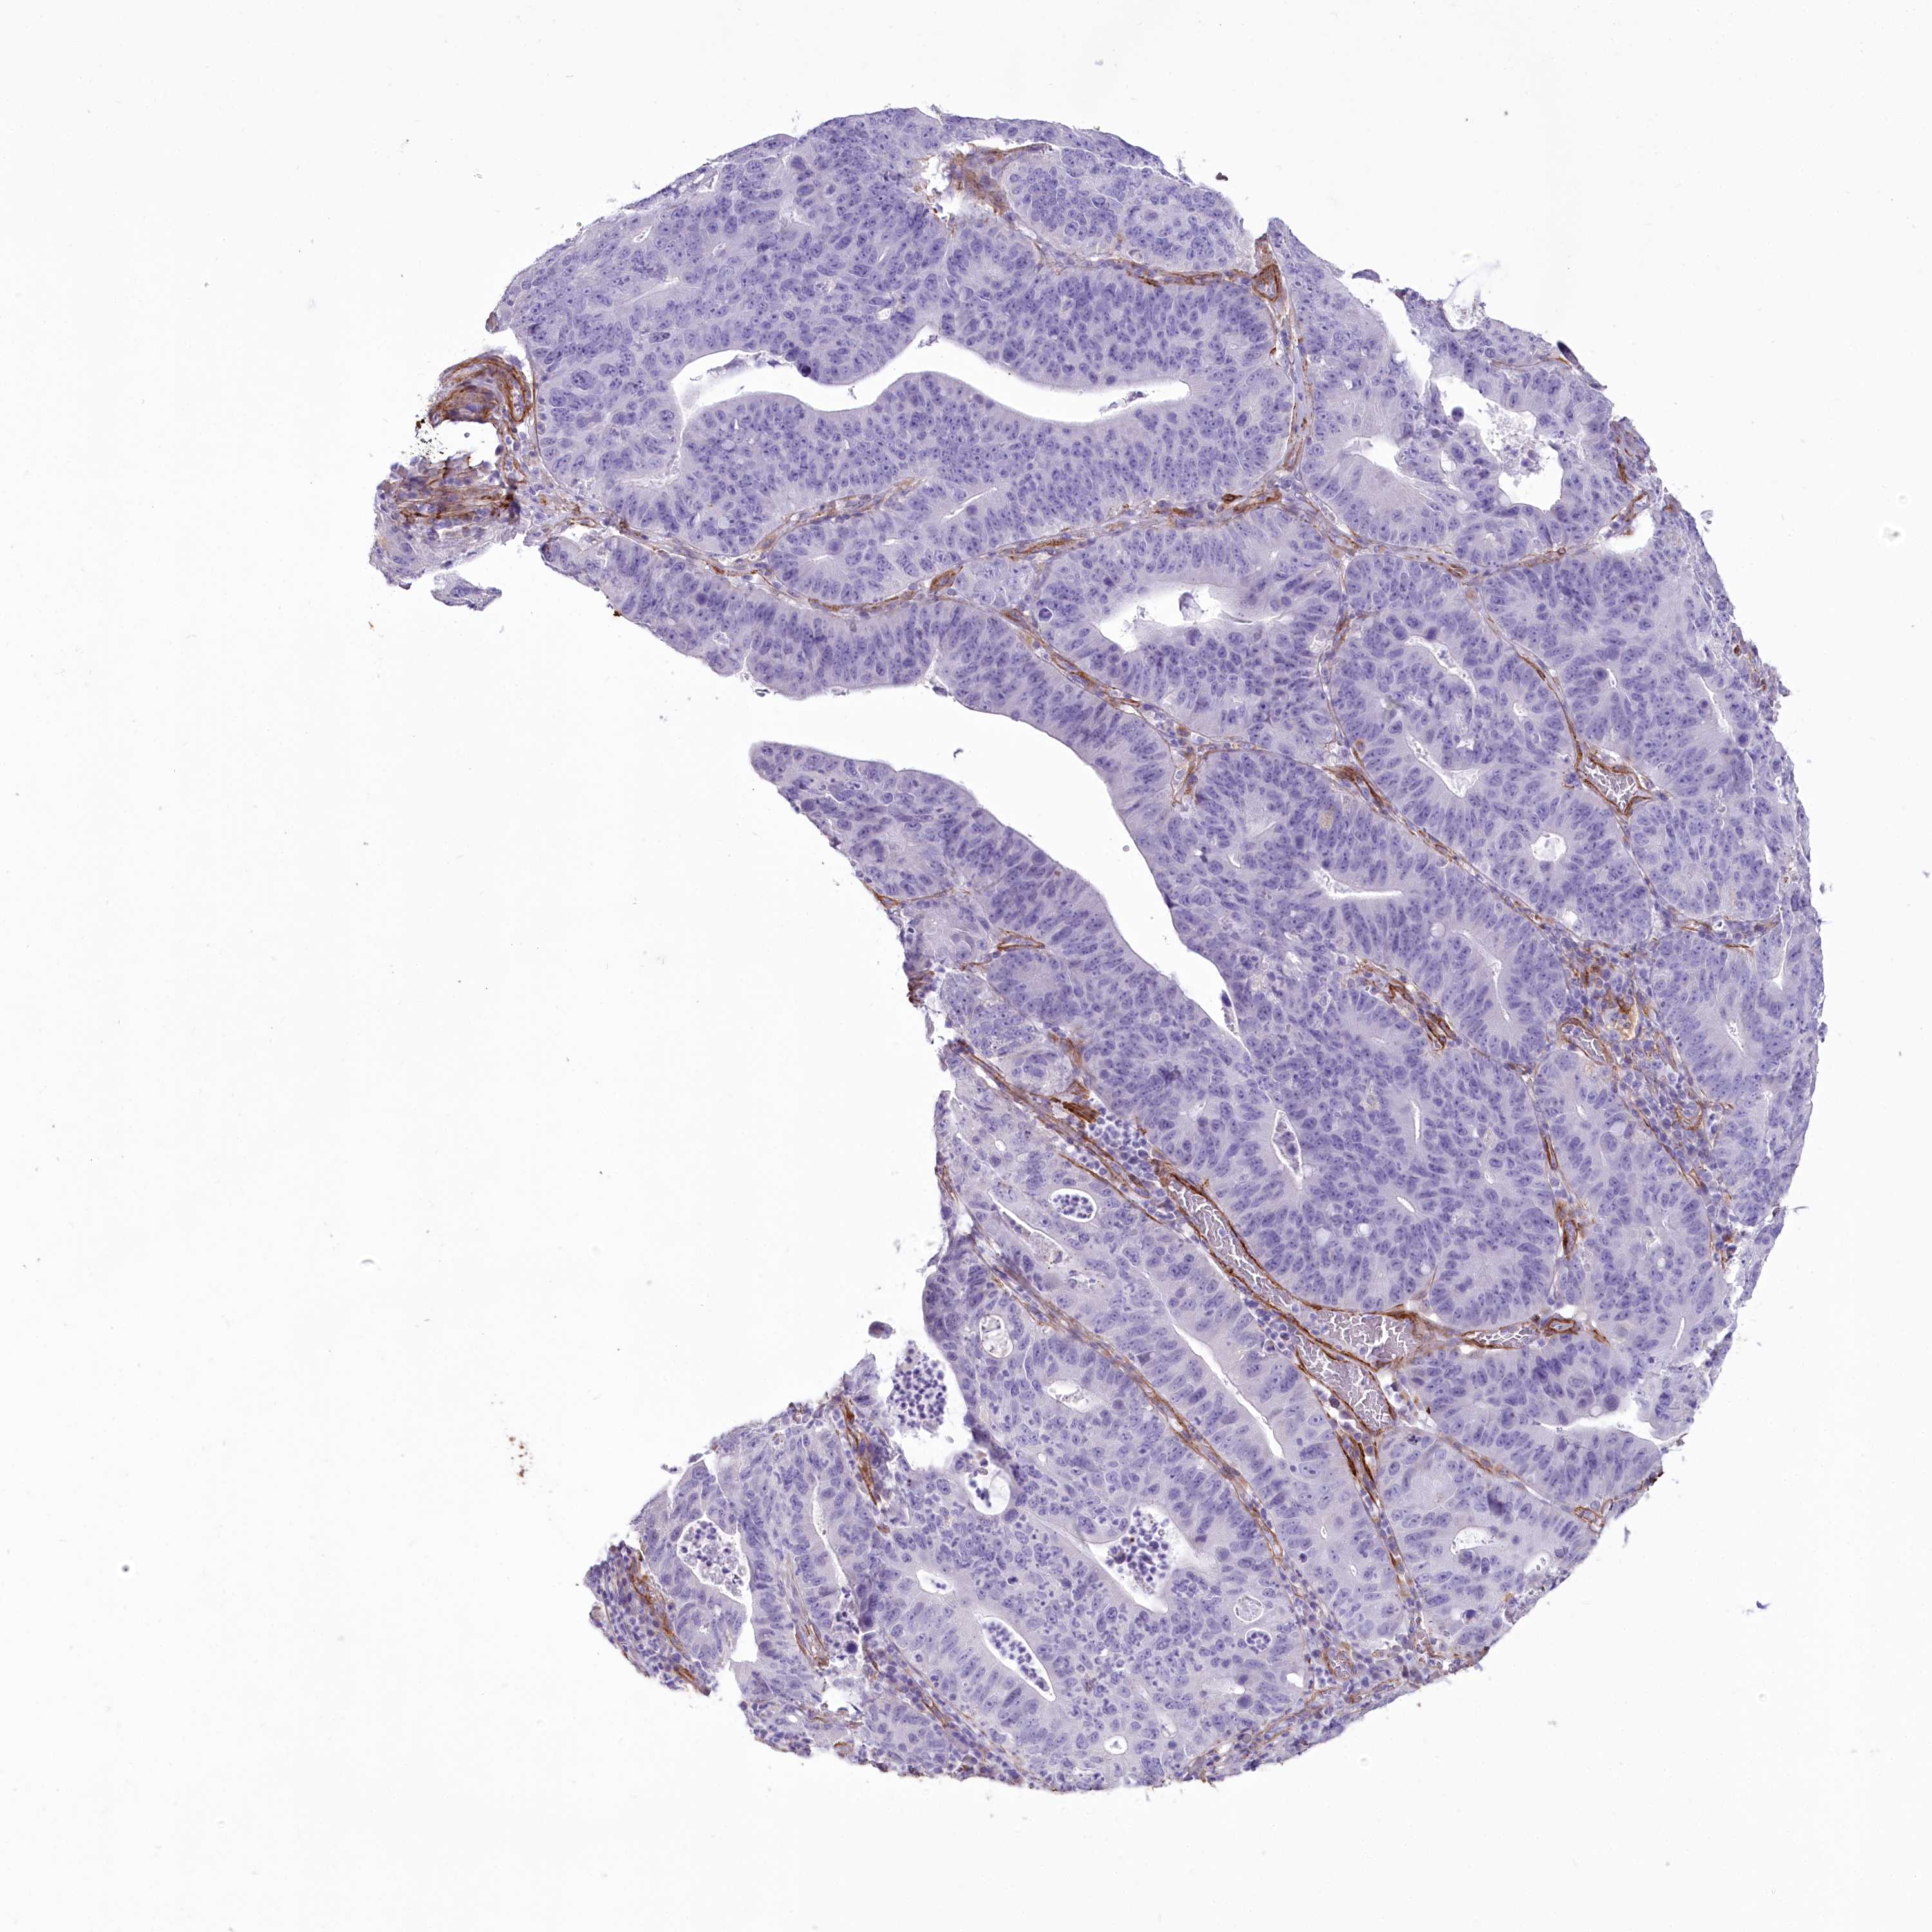

STOMACH CANCER - Protein expressioni

A mouse-over function shows sample information and annotation data. Click on an image to view it in a full screen mode. Samples can be filtered based on level of antibody staining by selecting one or several of the following categories: high, medium, low and not detected. The assay and annotation is described here.

Note that samples used for immunohistochemistry by the Human Protein Atlas do not correspond to samples in the TCGA dataset.

Antibody stainingi

Antibody staining in the annotated cell types in the current human tissue is reported as not detected, low, medium, or high, based on conventional immunohistochemistry profiling in selected tissues. This score is based on the combination of the staining intensity and fraction of stained cells.

Each image is clickable and will lead to virtual microscopy that enables deeper exploration of all samples and also displays staining intensity scores, fraction scores and subcellular localization as well as patient and tissue information for each sample.

Antibody HPA030665

Antibody HPA068563

Antibody CAB037231

Staining

High

Medium

Low

Not detected

Intensity

Strong

Moderate

Weak

Negative

Quantity

>75%

75%-25%

<25%

None

Location

Nuclear

Cytoplasmic/membranous

Cytoplasmic/membranous,nuclear

Adenocarcinoma, NOS